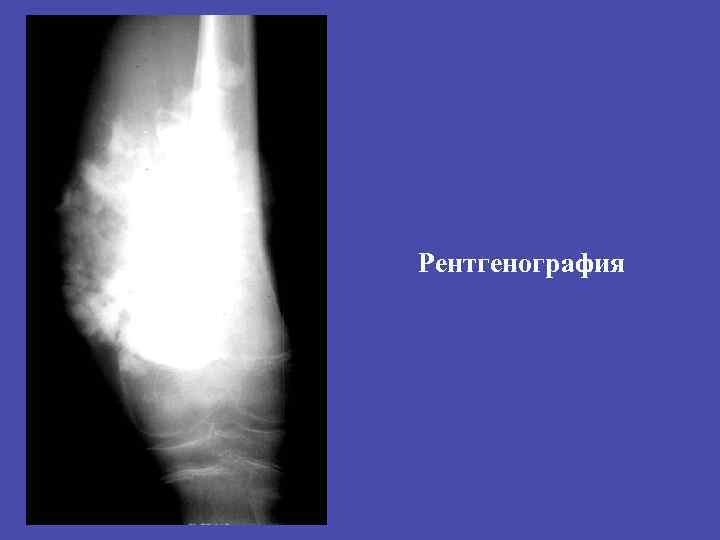

Злокачественные опухоли. üОстеогенная саркома üПараоссальная саркома üХондросаркома üОпухоли ретикулоэндотелиальной системы – саркома Юинга üРетикулосаркома üАнгиосаркома üЛипосаркома üГистиоцитоз

Злокачественные опухоли. Общие признаки злокачественных опухолей. • Деструкция кости без четких контуров. • Форма неправильная. • разрушение кортикального слоя. • Наличие мягкотканного компонента • Реакция надкостницы. • Быстрый рост и метастазы.

ЗЛОКАЧЕСТВЕННЫЕ ОПУХОЛИ: Остеогенная саркома - остеолитическая - остеобластическая Новообразование: -без четких наружных контуров - с наличием мягкотканного компонента 89

Остоегенная саркома остеолитическая и остоебластическая. üЛокализация зона активного роста – метафиз, метадиафиз длинных трубчатых костей. Изолированно диафиз не поражается. Через хрящ не переходит. üКозырек Кодмена – реактивный периостит. Спикулообразный периостит – костеобразование по ходу стенок кровеносных сосудов, проникающих в кость.

Остеогенная остеобластическая саркома 92

Остеогенная остеобластическая саркома Остеогенная остеолитическая саркома